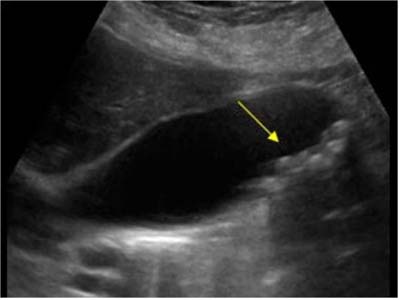

所谓“多发性胆结石”,一般是与“单发结石”区别而论的,就是指胆囊内不仅是一枚胆囊结石,而是可以探及多个或十多个,甚至数十个结石影像,称为“多发性胆结石”。B超影像中可发现多个强回声光团,可移动,后伴声影。

多发性胆结石超声影像